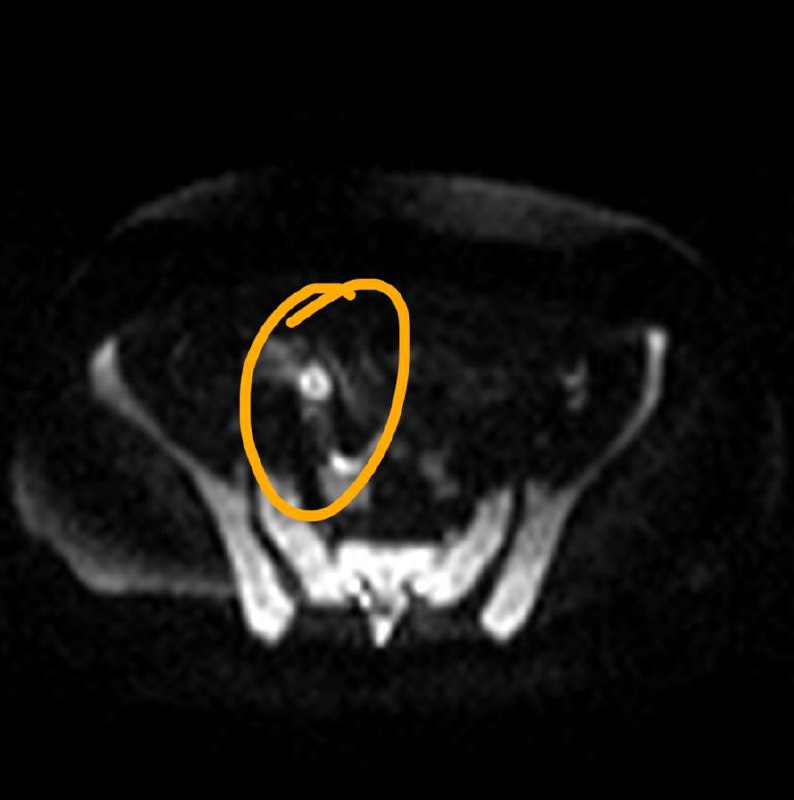

У пожилого мужчины после переохлаждения резко появилась задержка мочеиспускание, урологи утверждают, что у него – острый простатит. А на Магните – типичный рак, по крайней мере, PI-RADS 5.

Как считаете, может ли острый простатит выглядеть вот так? Асимметричный, с достаточно чётким контуром, да ещё и с быстрым накоплением контраста и быстрым же его вымыванием?

Что-то я сильно сомневаюсь, поделитесь опытом.

Когда рак простаты видно вот так, как здесь - исследование не вызывает отвращения, в отличие от случаев, когда приходится писать PIRADS-3..

Другое дело, что мы ж о пациентах заботимся, а не о себе, любимых, и каждый PIRADS-3 для пациента, все же, лучше, чем легко и непринуждённо обнаруживаемый, как в данном случае, PIRADS-5.

Пожелаем этому мужчине 75 лет успехов в лечении и минимума неприятных ощущений, которыми, неизбежно, такое лечение сопровождается.